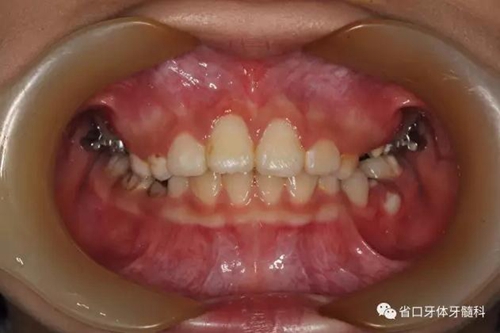

口內(nèi)情況:正面觀

口內(nèi)情況:牙合 面觀